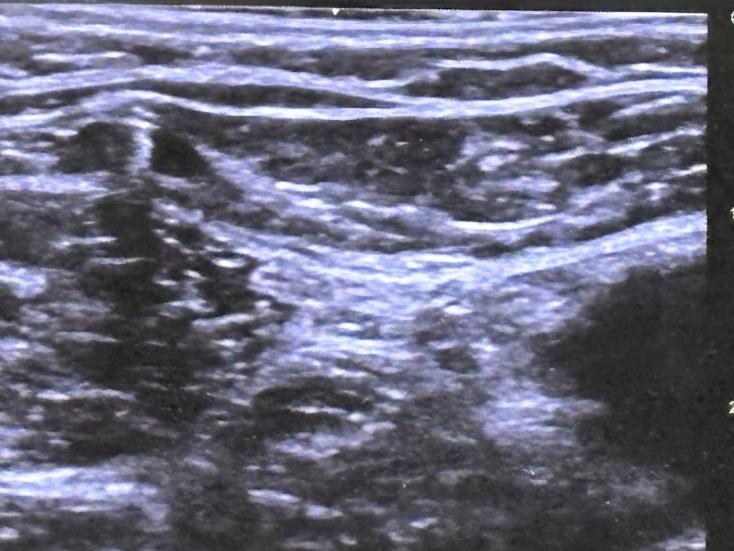

Image

Echodoppler avec un médecin Angiologue

Il faut en parler avec votre médecin traitant qui va vous prescrire un echo-doppler veineux des membres inférieurs. Idéalement il faut faire cet examen par un angiologue / phlébologue ou un médecin vasculaire Le but de l’examen est d’explorer le réseau veineux des membres inférieurs à l’aide d’ultrasons. Le praticien va commencer par étudier le réseau veineux profond afin de vérifier son bon fonctionnement. Puis il ou elle va rechercher la ou les veines intermédiaires responsables de la stagnation veineuse. On parle de veines incontinentes. Il s’agit essentiellement des veines saphènes et des perforantes.